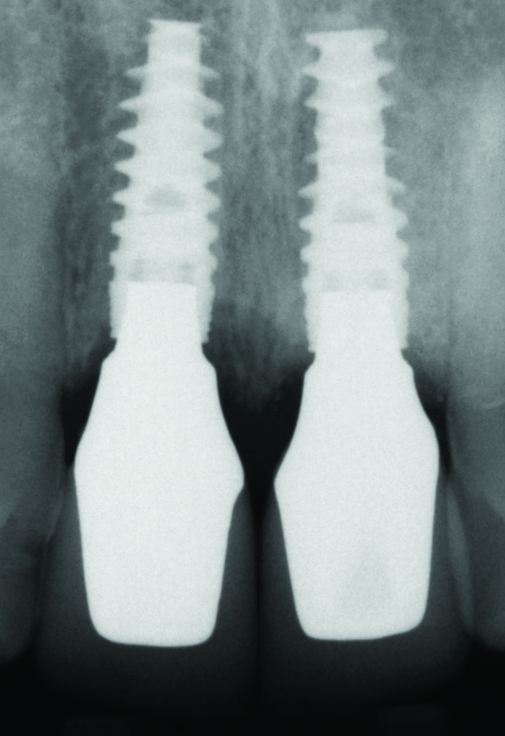

Fig 28. Radiograph on the day of surgery: Implant placement and provisional restoration. Note that the implants are subosseous, as their position is defined by the desired facial free gingival margin position.

Figure 28

Fig 29. One-year radiograph of the definitive restorations on the implants Nos. 8 and 9. Note the crestal bone stability compared to the radiograph taken on the day of surgery in Figure 28.

Figure 29

In the final case, adjacent implants were placed in healed sites No. 8 and No. 9 and provisionalized at the time of surgery (Figure 27 and Figure 28). This case illustrates the effect of platform switching on bone and gingival tissue stability, as well as recognizing that appropriate diameter and spacing is important to maintain ideal ridge contour. The gingival tissue anatomy between implants is characteristically shorter than papilla form between adjacent teeth, and, as a consequence, it is important to incorporate implant designs and procedures that minimize bone-level changes and associated soft-tissue recession. The depth of implant placement was subcrestal relative to the ridge crest, based on the future desired free gingival tissue level, while allowing prosthetic running room. The studies of Barros et al and Veis et al noted that implants positioned subcrestally (as seen in Figure 29) showed better crestal bone preservation than those placed equicrestally or supracrestally.28,29 The implant design used in this case achieves excellent primary stability. Along with the optimal 3-dimensional positioning of the implants and, specifically, the subcrestal placement, as well as the immediate provisionalization protocol, these concepts and implants have contributed to a pleasing esthetic outcome, as seen in Figure 30.